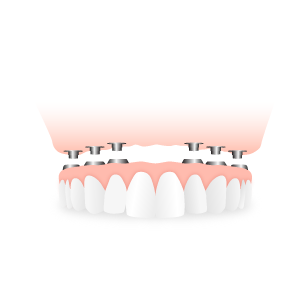

ALL ON 6

All on 6 predstavlja isto krunice, ali na ugrađenih 6 implantata, što je mnogo bolje, jer se na veći broj implanta bolje prenose sile žvakanja.